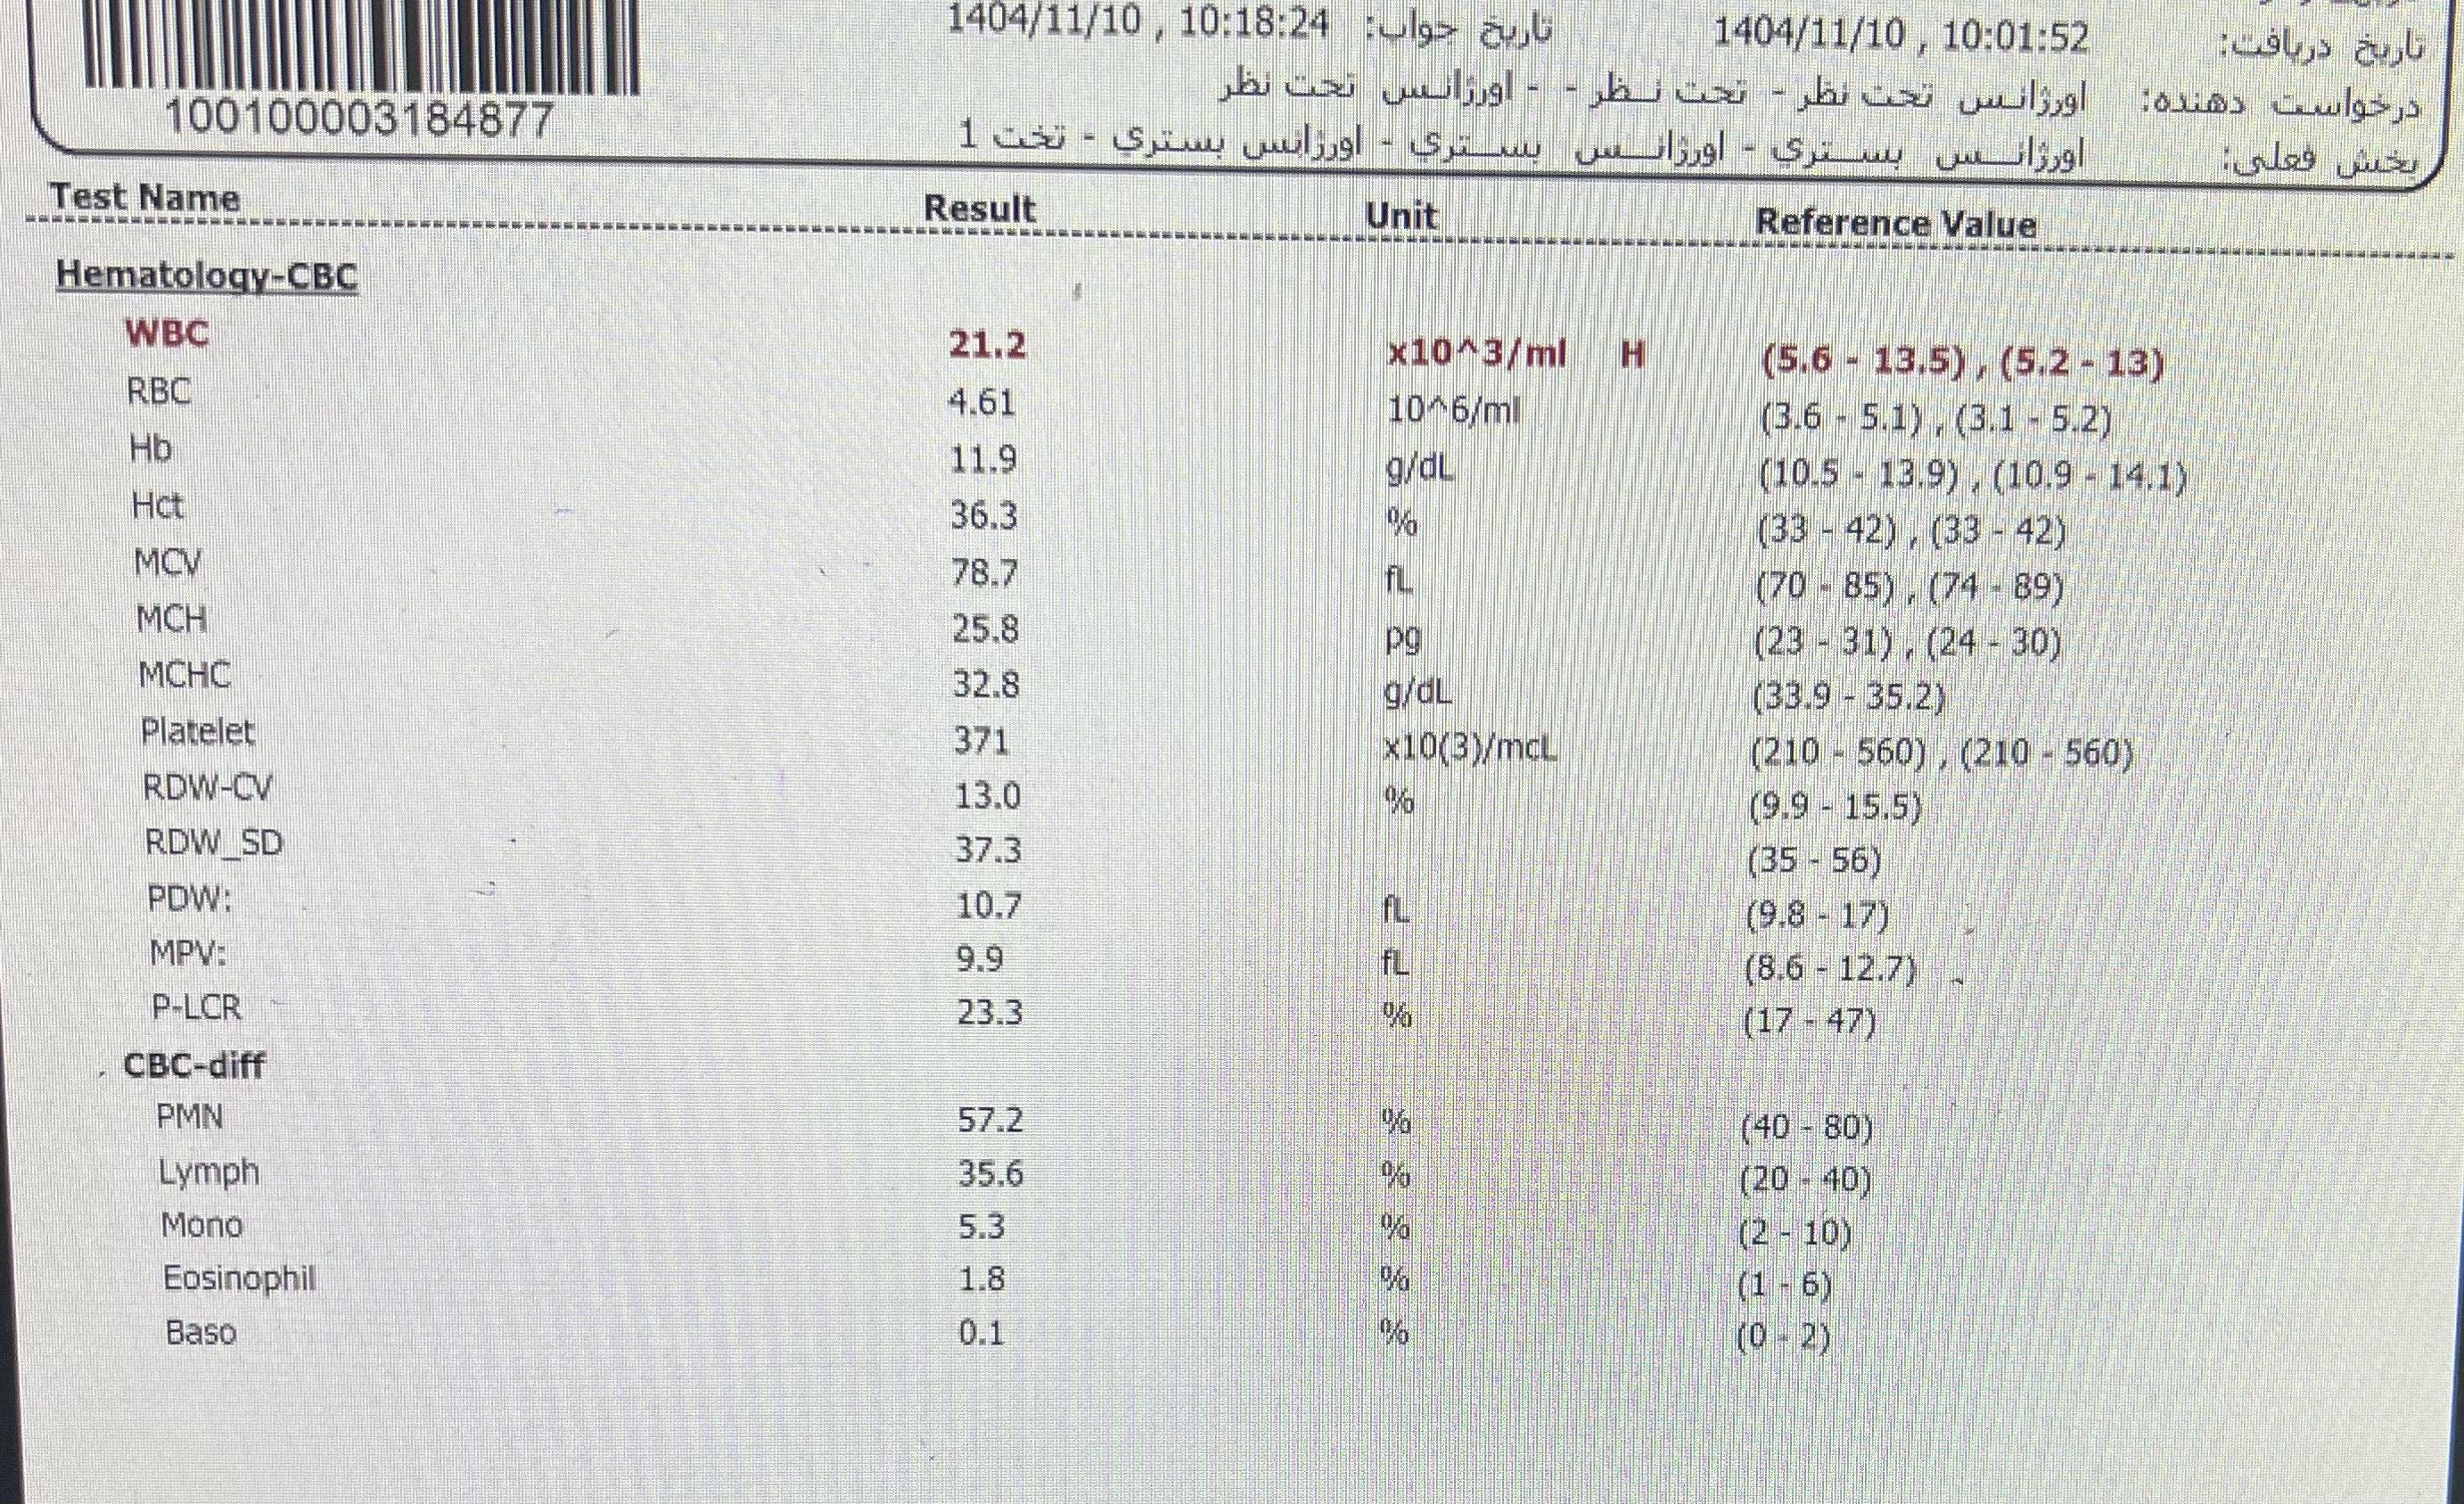

CBC diff